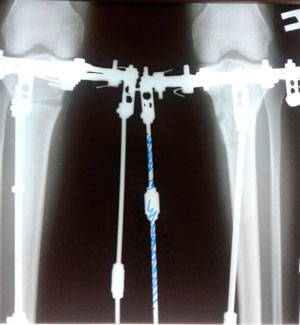

Дата операции - 05.07.2019г.

Дата снятия аппаратов - 13.09.2019.

Срок сращения - 71 день.